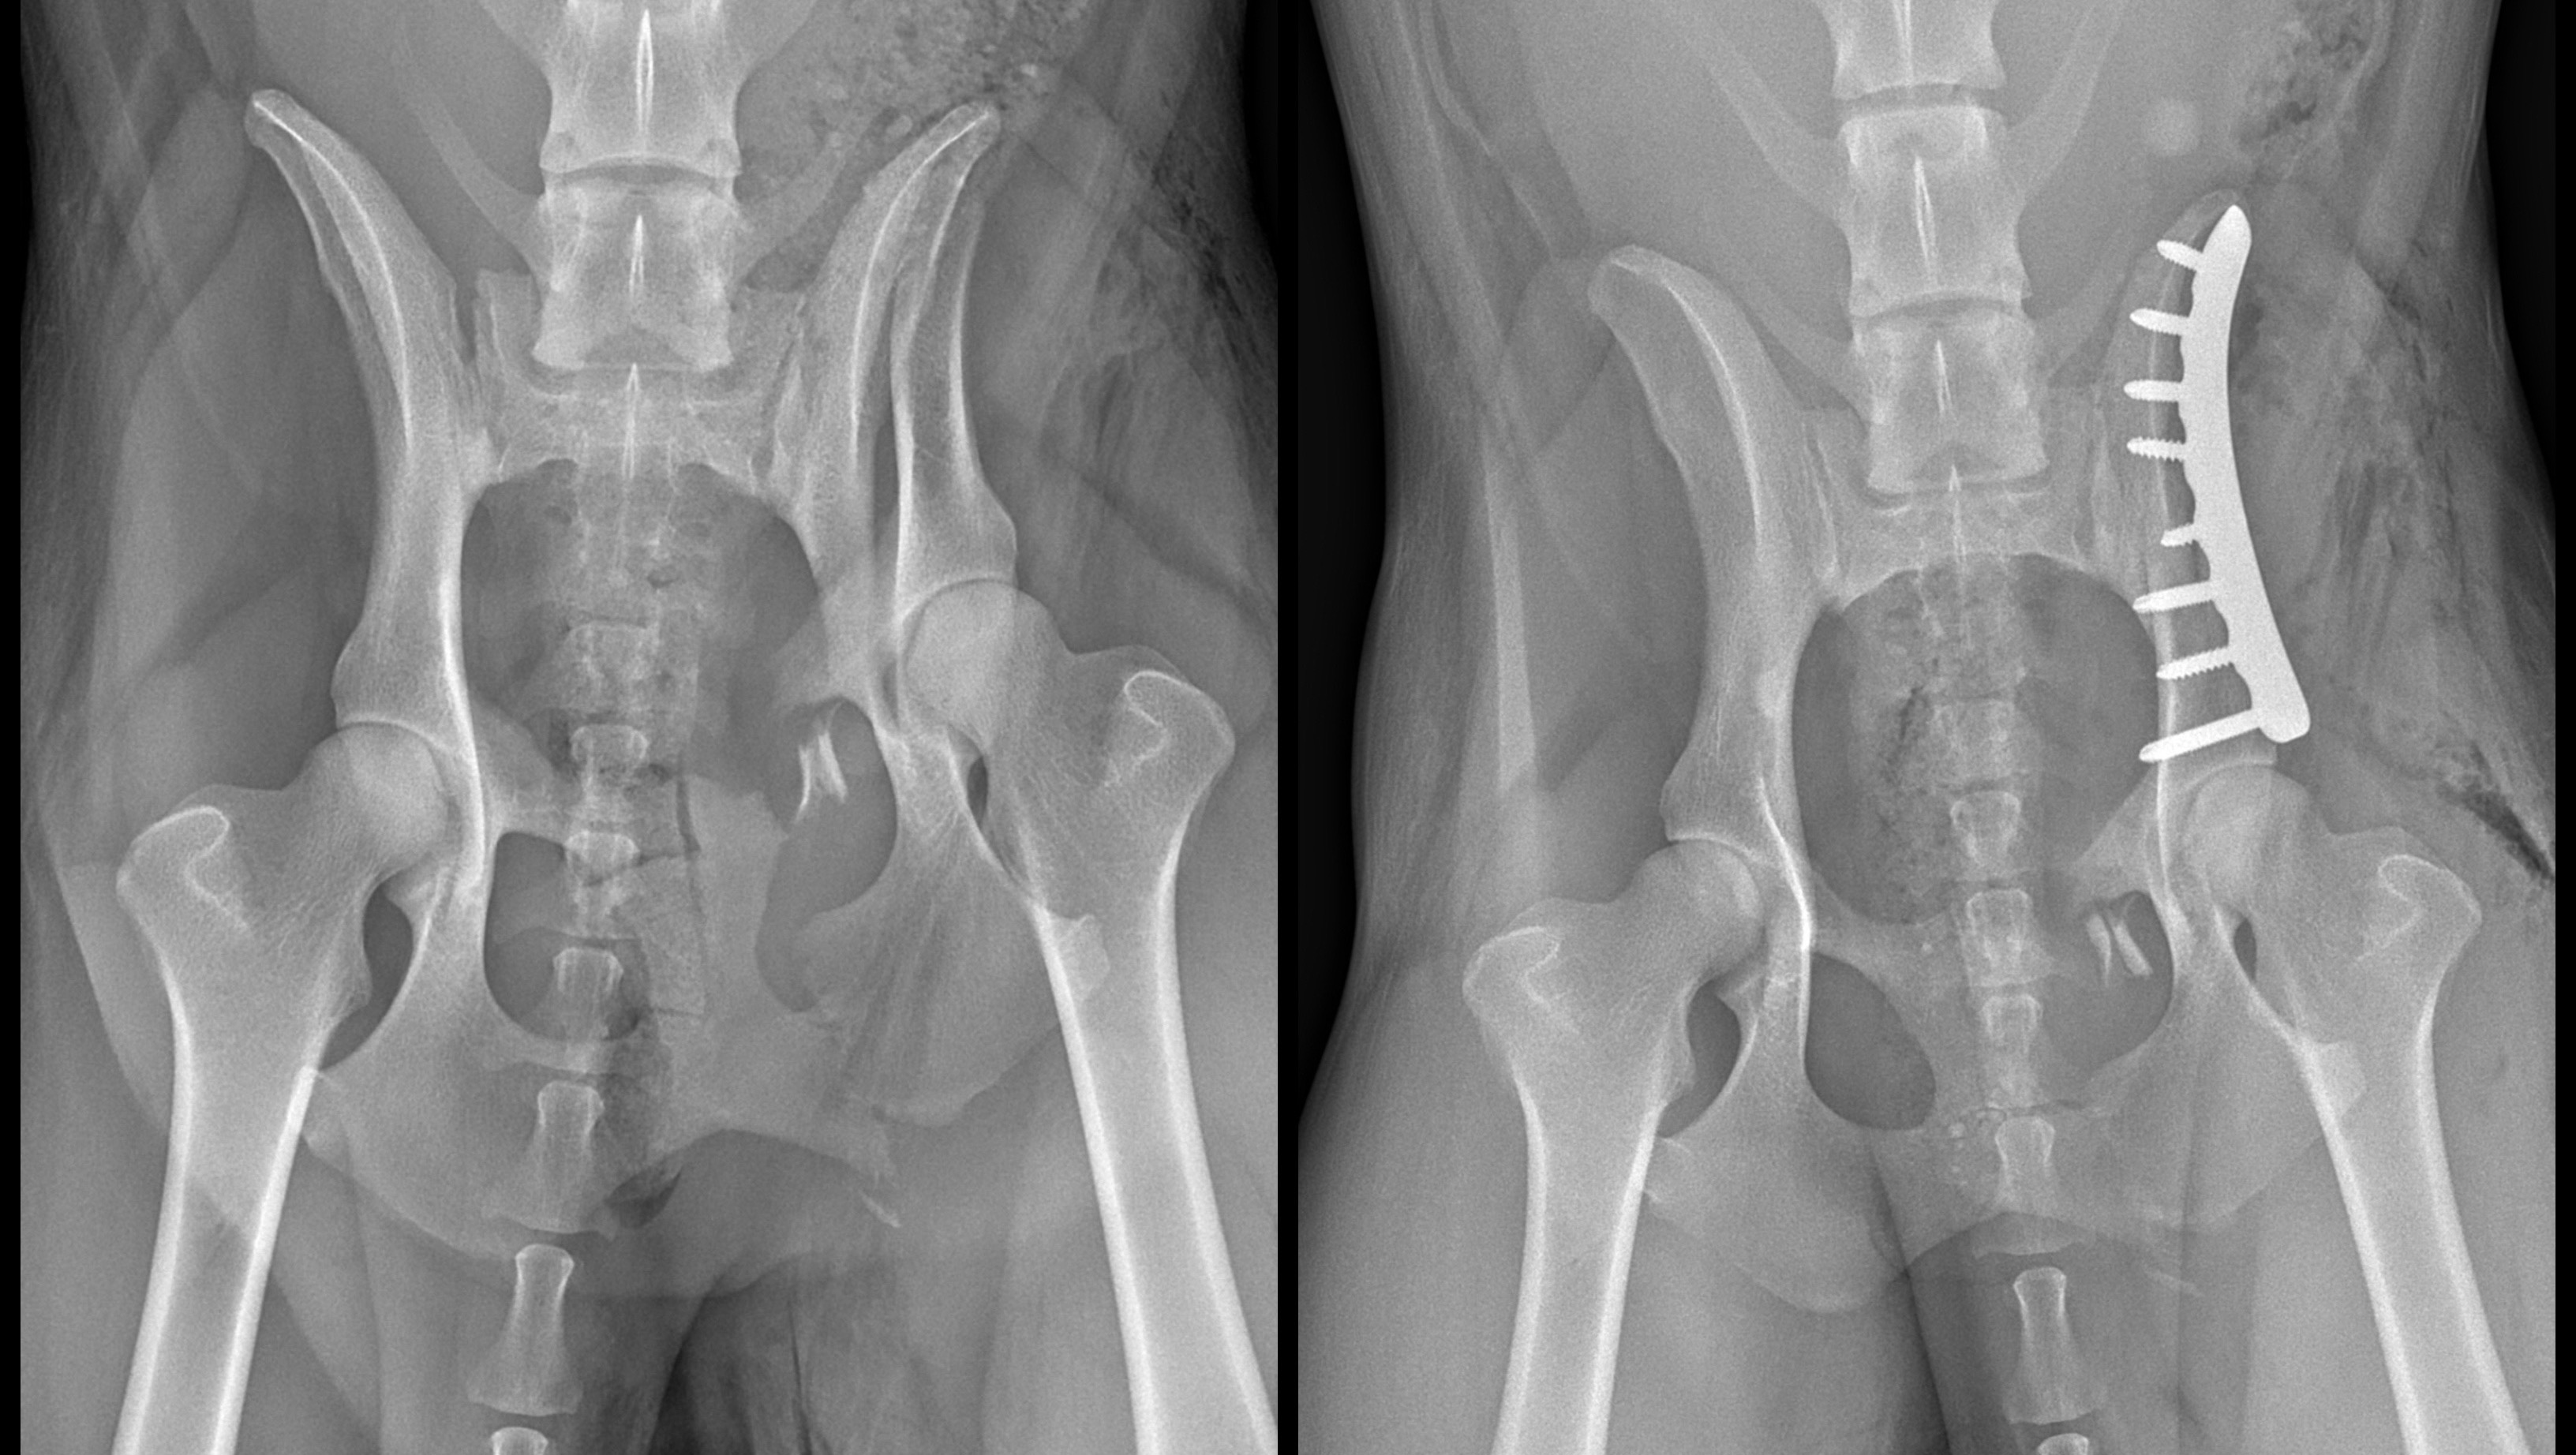

Hi! I am Mako’s partner and protector (well, “owner,” as many would say) Noelle. Last weekend, my adventure companion and working k9 Mako sustained a serious injury while we were recreating in the mountains. This accident (absolutely no fault of little Mako’s) resulted most notably in several fractured pelvic and pubic bones, requiring a plate to be put in, and the rest of the fractures are intended to fuse with rest.

(Pre-surgery fractures on the left, post-surgery xray on right).